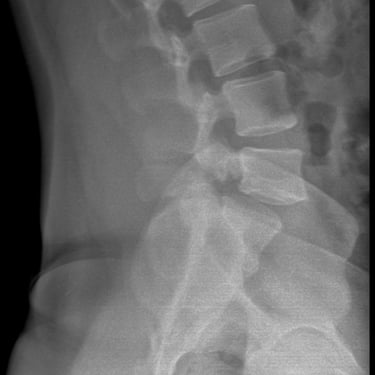

Listesis Lumbar L5–S1 por Fractura Ístmica: Estabilización con FTP y TLIF

La listesis lumbar L5–S1 por fractura ístmica se produce por un defecto en la pars interarticularis que genera inestabilidad vertebral, dolor lumbar crónico y compromiso radicular. Cuando el tratamiento conservador no es efectivo, la artrodesis lumbar con fijación transpedicular (FTP) asociada a la fusión intersomática transforaminal (TLIF) es una alternativa quirúrgica eficaz. Este procedimiento permite descomprimir las raíces nerviosas, restaurar la alineación vertebral y lograr una fijación sólida del segmento afectado. La combinación de estabilización y fusión reduce el dolor, mejora la función y favorece una recuperación segura y progresiva.